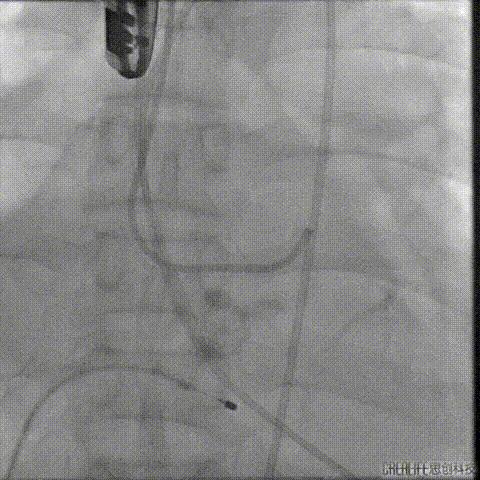

经桡冠脉保护

置入Venus-A32号瓣膜并释放

复查造影

撤出冠脉保护

再次复查造影